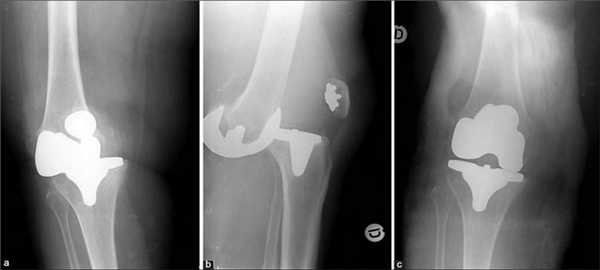

Две техники операции у одного пациента.

Типы протезов и связанные с ними методики

Вы уже знаете, что бывает полное и частичное эндопротезирование коленного сустава, где в первом случае лечение подразумевает полноценную замену суставных поверхностей, а во втором - имплантацию поврежденного участка одного из мыщелков. Соответственно, протезы классифицируются на тотальные, одномыщелковые и ревизионные для замены импланта.

- После постановки однополюсной системы максимально сохраняется собственный костно-хрящевой сегмент и не затрагиваются связки, кстати, они должны быть в хорошем состоянии.

Одномыщелковая замена сустава на рентгене.

Сравнение двух типов операций.

С каждой последующей операции статистика успешности ниже. Импланты при этом становятся все более громоздкими.

Одномыщелковое протезирование подразумевает срок службы небиологического устройства максимум 7 лет. Тотальное замещение предусматривает время службы вживленного механизма от 15 лет. Ревизионное переносится сложнее, а риск инфекции и других негативных явлений почти в 2 раза выше, чем после первичной операции.